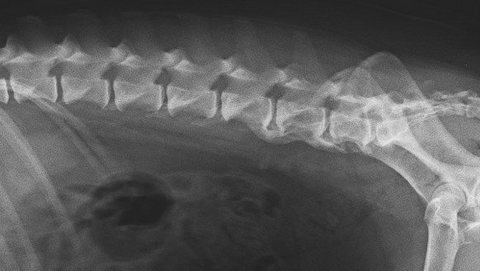

Spondyloseeim Hund

Die Spondylose zählt zu den degenerativen Skeletterkrankugen. Man versteht darunter die Knochenspangenbildung zwischen zwei Wirbelkörpern.

Häufig beginnt der Umbauprozess an der Unterseite der Wirbelkörper. Das umliegende Gewebe ist meistens chronisch entzündet. Da auch die Wirbelzwischenräume von knöchernen Zubildungen und Überbrückungen betroffen sein können, kann dies zu einer Versteifung einzelner Abschnitte der Wirbelsäule führen.

Kommt es zu verwachsenen Knochenbrücken zwischen den einzelnen Wirbelkörpern, nehmen die Schmerzen etwas ab. Allerdings bleibt ein steifer Rücken zurück.

Bilden sich Zubildungen in erheblichem Ausmaß im Seitenbereich der Wirbelkörper, kann auch bis in die Region der Nervenabgänge betroffen sein. Somit kann bei einer fortgeschrittenen Spondylose auch eine Problematik in der Hinterhand auftreten, da die Leitfähigkeit der Rückenmarksnerven gestört ist.